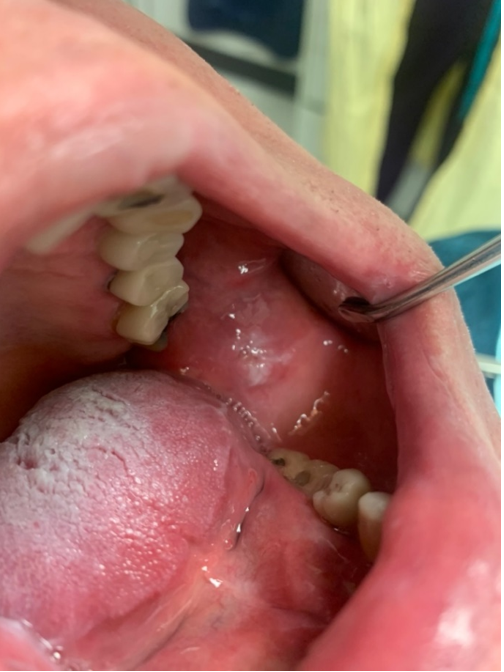

A 78-year-old male patient initially presented to the Dental College of Georgia at Augusta University for periodontal implant therapy and prophylaxis appointments. During clinical examination, several incidental clinical findings such as xerostomia, coated tongue, abnormal bilateral white lesions, and hyper-keratinization on the lateral borders of the tongue (Figure 1) and buccal mucosa (Figure 2) were noted. These findings were consistent with patient’s known history of Pachyonychia Congenita, previously affecting his skin, nails (Figure 3), and mucous membranes.

Given the patient’s history and concerning clinicals findings, a consultation was made with the Oral Pathologist and an excisional biopsy on the lateral borders of the tongue and buccal mucosa was recommended to rule out pre-cancerous lesions or other pathological conditions that may be related to the patient’s symptoms.

A punch biopsy of 4 mm diameter and 4mm depth was performed on the patient and the samples were taken from two locations: lateral border of the tongue on the right side and left buccal mucosa. 4-0 chromic gut sutures were used for wound closure and the obtained samples were placed in formalin and sent for pathological evaluation.

Figure 1: Hyperkeratosis on the lateral border of the tongue